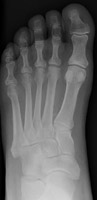

A | AP radiograph of the foot. The typical appearance of Freiberg's infarction. |

Freiberg's Infarction |

This is a form of avascular necrosis. It is idiopathic (possibly post-traumatic). The process typically affects the second metatarsal head and is unilateral.